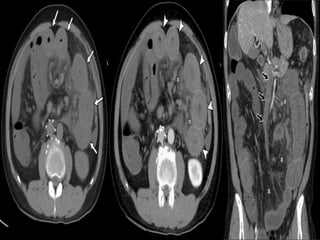

CHRONIC MESENTRIC ISCHEMIA

WITH VASCULAR CALCIFICATION

WITH VASCULAR COLLATERALS

Computed tomography  Usedto for -screening the patients with suspected chronic mesenteric ischemia -Calcified plaque. -collateral vessels.

• 85.

CHRONIC MESENTRIC ISCHEMIA WITHVASCULAR CALCIFICATION CHRONIC MESENTRIC ISCHEMIA WITH VASCULAR COLLATERALS